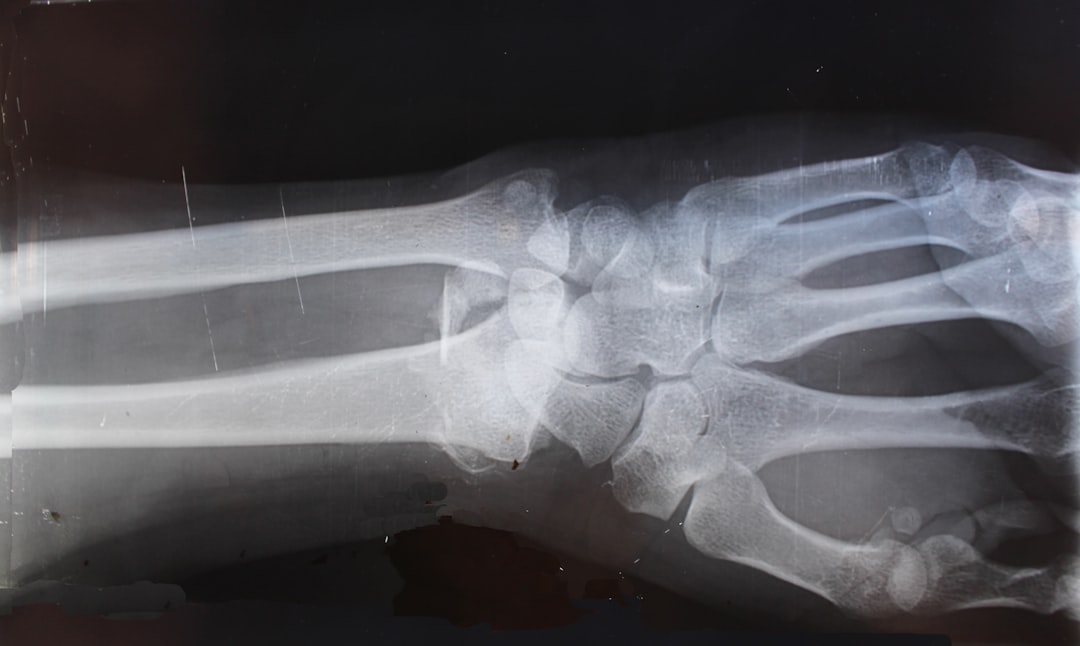

Diagnostics

On-site X-ray and laboratory services for accurate diagnosis.